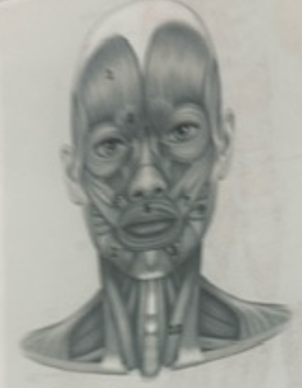

What muscle is 1?

Frontalis

What muscle is 2?

Depressor anguli oris

What muscle is 3?

Depressor labili inferioris

What muscle is 4?

Corrugator supercili

What muscle is 5?

Orbicularis oris

What muscle is 6?

Zygomaticus minor

What muscle is 7?

Zygomaticus major

What muscle is 9?

Buccinator

What muscle is 10?

Sternocleidmastoid

What muscle is 11?

Temporalis

What muscle is 12?

Masseter

What muscle is 13?

Risorius